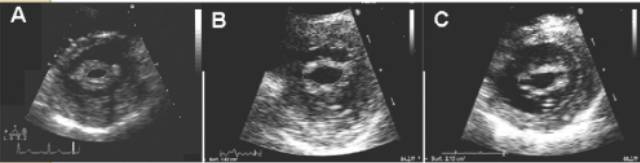

操作方法:首先要获取胸骨旁的左心室短轴,获取二尖瓣口的切面,然后在二尖瓣口的內缘描记获取二尖瓣口的解剖面积。在进行测量时,为了避免高估二尖瓣口的面积,我们应该尽量让我们的扫查切面位于二尖瓣瓣尖的水平。